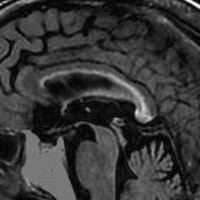

70歳女性の右後頭葉退形成性星細胞腫に対して,摘出術と54グレイ27分割の局所放射線治療をしました。右後頭葉に腫瘍摘出腔があって腫瘍再発はないのですが,治療一年後くらいから脳梁の脳室側にFLAIRで高信号の領域が広がってきました。特に星細胞系腫瘍の場合に,局所浸潤再発とまがうような所見となることもあります。ここにあげた例は典型的なもので,脳梁膨大部から膝部に至るまで脳梁内側部の白質変性が明瞭にとらえられます。